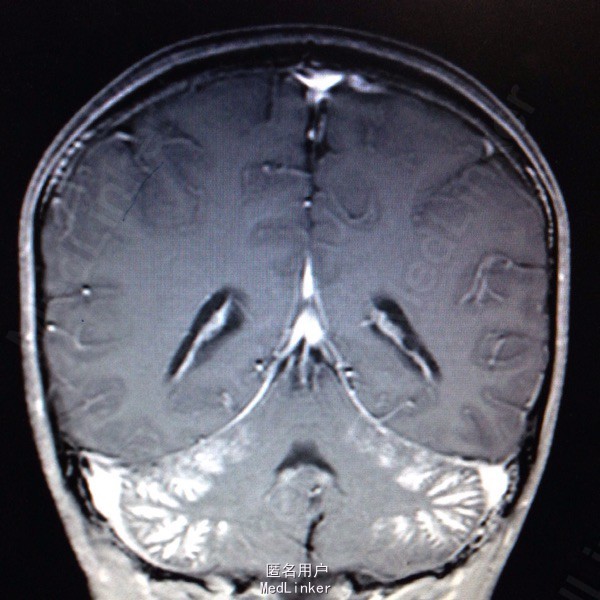

查体:面罩吸氧,甚至浅昏迷,CRT 2s,双侧瞳孔等大等圆,直径约4mm,对光反射迟钝,口唇红润,双肺可闻及干啰音,四肢肌张力偏高,以左侧为主,病理反射Babinski征阳性。辅查:血气分析提示碳氧血红蛋白8.4%,急诊行高压氧治疗,血常规:白细胞14.48G/L,血红蛋白120g/L,血小板291G/L;头颅MR检查:1.双侧小脑半球皮层及皮层下多发脑回样强化,双侧基底节区斑片状强化,结合病史资料,考虑一氧化碳中毒引起;2.双侧乳突炎症。

一氧化碳中毒脑病时多损伤基底节区、额叶、颞叶,本病例除基底节区损伤外,双侧小脑半球皮层及皮层下也受累,临床上还是比较少见的。